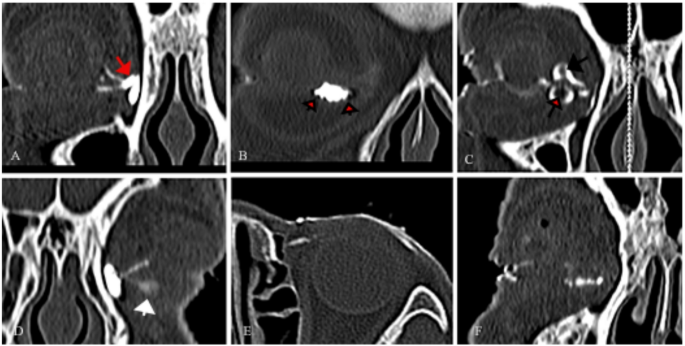

CT-DCG imaging features of primary canaliculitis. (A) The dilation of the common canaliculus (red arrow). (B) Canalicular dilation towards the temporal side with filling defects in close proximity to the canalicular lumen wall (short black arrow). (C) Both the upper and lower canaliculi showed canalicular dilation and central radiolucency with marked surrounding enhancement (long black arrow). (D) Temporal dilation of the lower canaliculus, accompanied by small filling defects (white arrow). (E) Raggedness of the canalicular lumen wall. (F) A beading appearance of the lower canaliculus.

CT-DCG imaging features of primary canaliculitis.(A) Canalicular dilation towards the temporal side with both types of filling defects. (B) Dilations involved the entire length of the upper and lower canaliculi with both types of filling defects. (C) Dilation and filling defects of the canaliculus accompanied by dilation of the lacrimal sac (black arrow). (D) A skin fistula connected to the affected inferior canaliculus (red arrow). (E) The diverticulum formed on the temporal side of the canaliculus (thin white arrow). (F) The diverticulum formed below the vertical segment of the lower canaliculus (thick white arrow).

Within the canaliculitis group, 127 canaliculi exhibited dilation. Among these dilated canaliculi: 56 showed dilation near the vertical segment, extending to varying degrees toward the temporal side (Fig. 3D); 40 demonstrated dilation in the proximal two-thirds of the horizontal segment (Fig. 3F); 10 had dilation at the distal end, adjacent to the common canaliculus (Fig. 3A); and 21 displayed dilation involving the entire length of the canaliculus (Fig. 4B).

Filling defects were observed in 110 canaliculi, categorized as follows: 38 defects adjacent to the canalicular lumen wall (Fig. 3B); 47 with central radiolucency and marked surrounding enhancement (Fig. 3C); and 25 with both types of defects (Fig. 4A and B).

Additional imaging findings included: a “beading” appearance in 41 canaliculi (Fig. 3F); small diverticula in 13 canaliculi (Fig. 4E and F); a “ragged” lumen wall in 35 canaliculi (Fig. 3E).